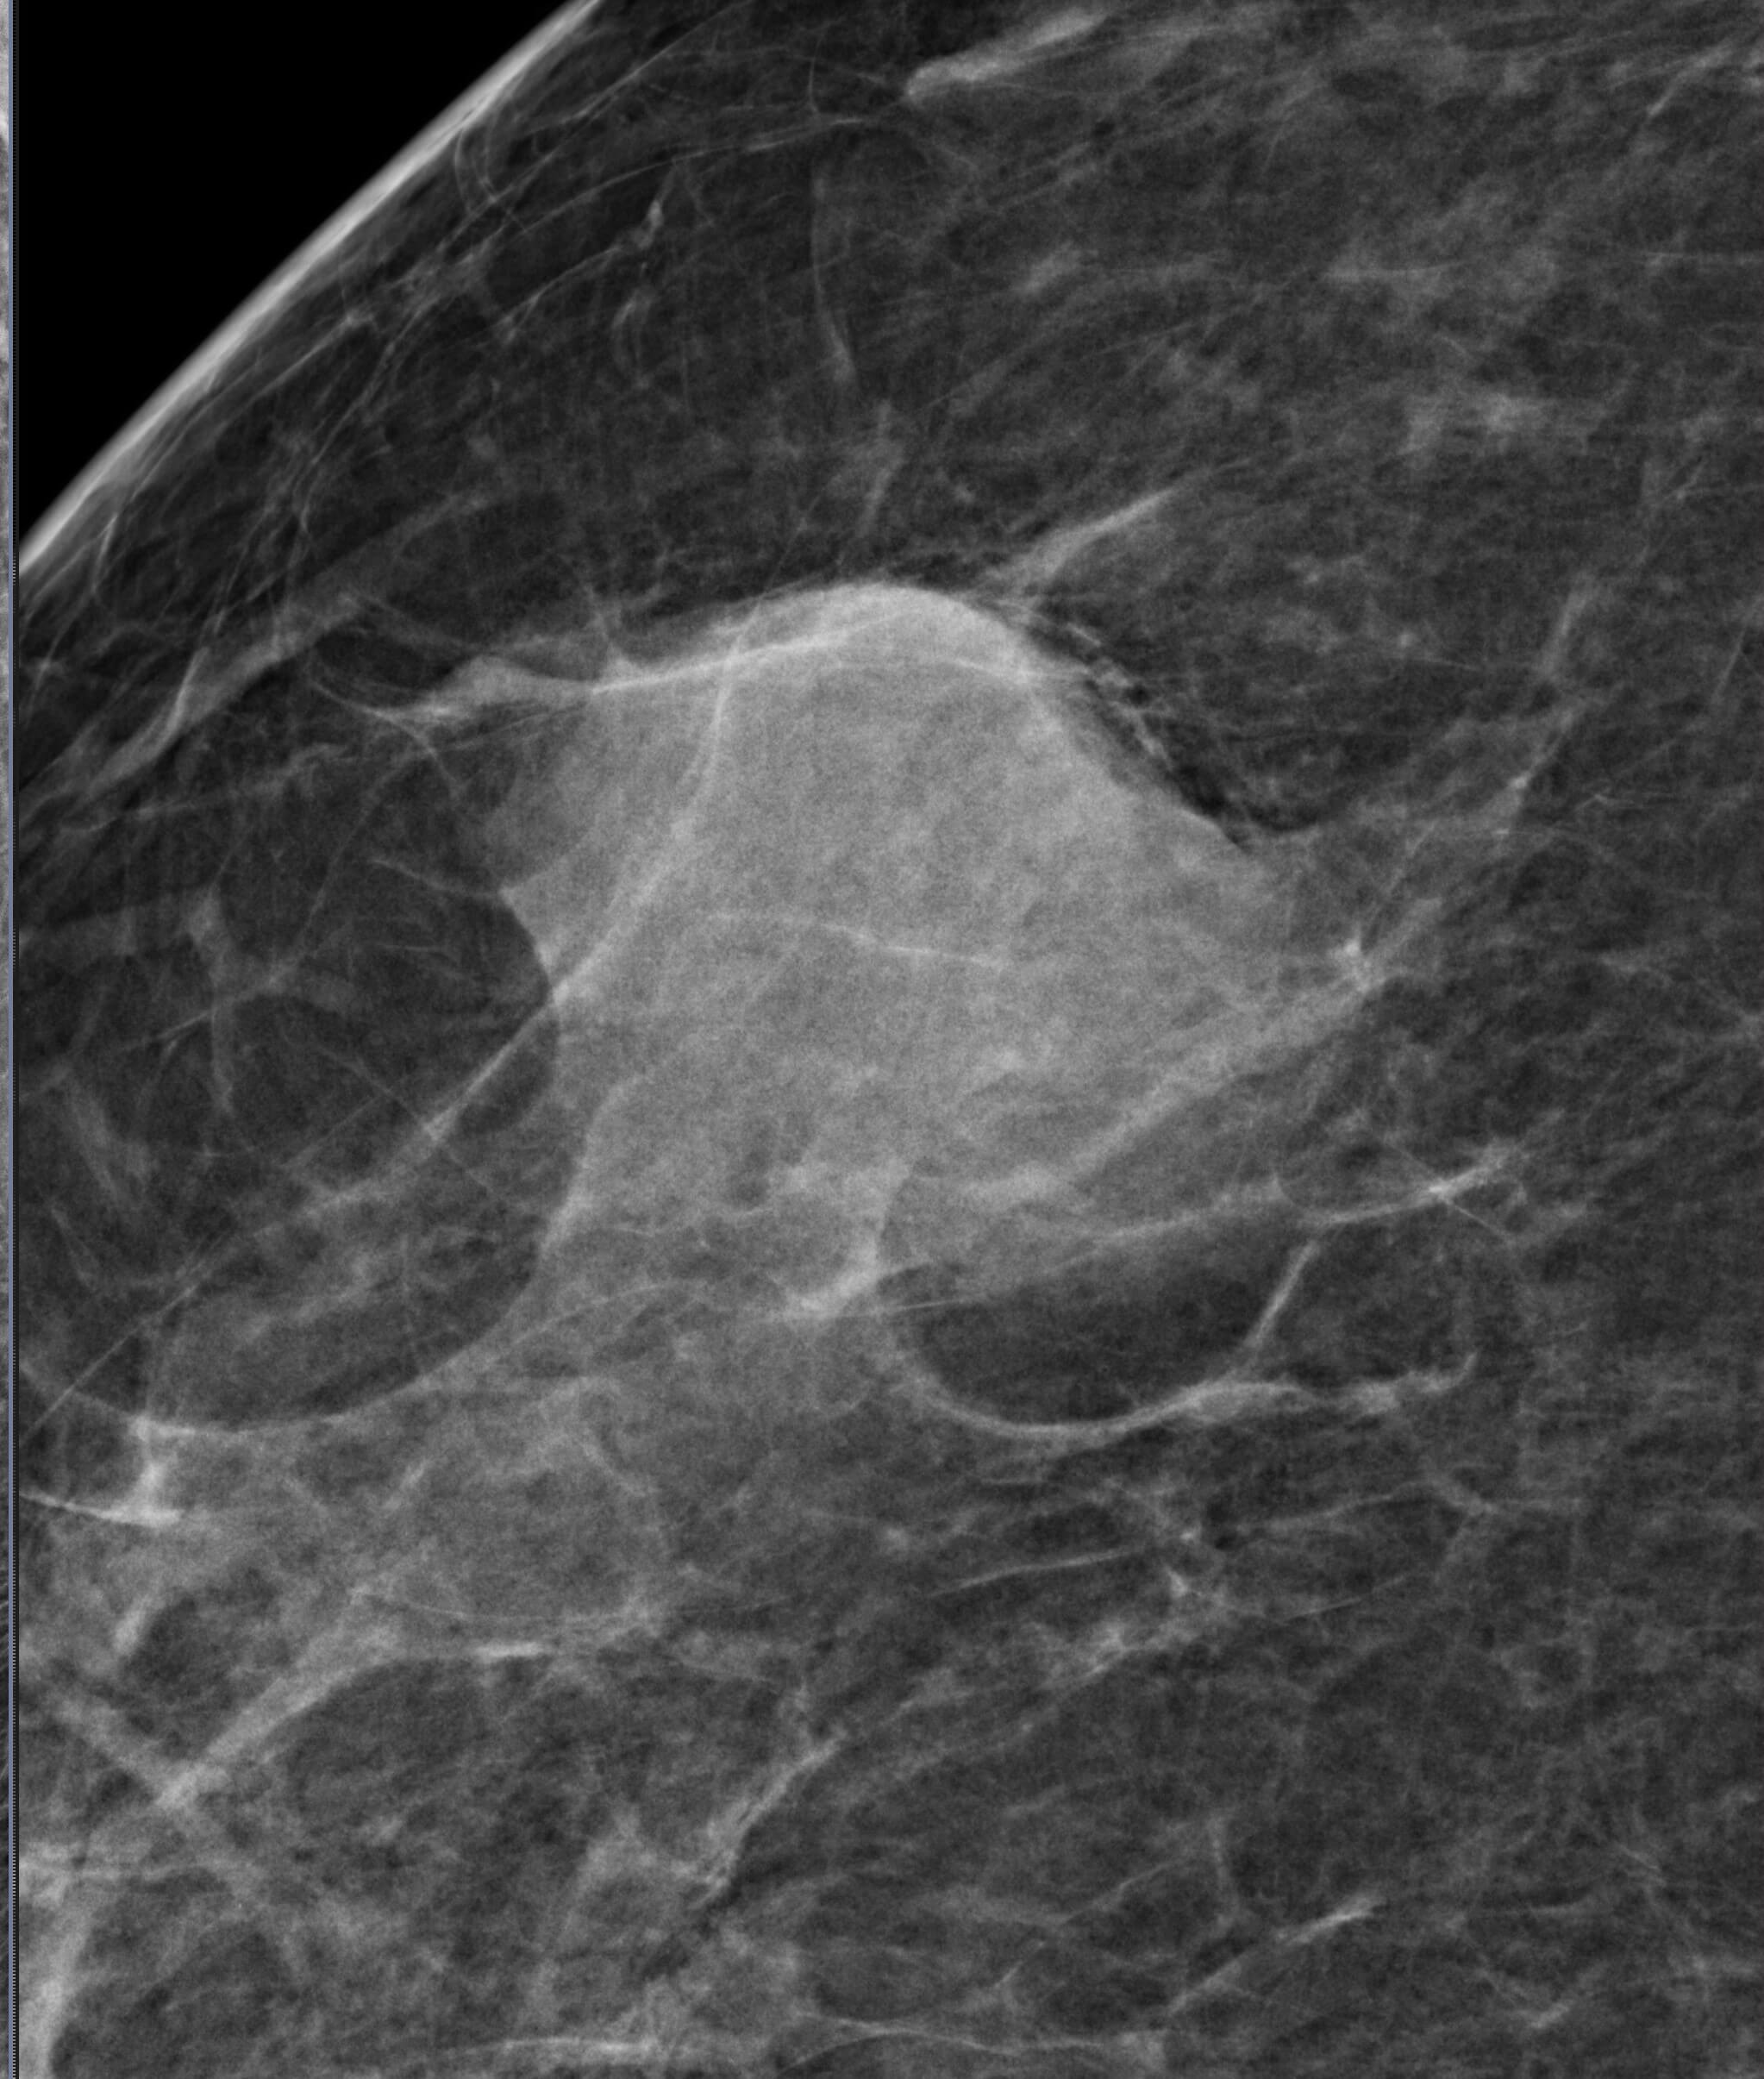

Mammogram revealed the presence of an irregular high density mass in the posterior third of the upper outer quadrant of the right breast with indistinct margins on two-dimensional mammogram. No internal calcification seen. No overlying skin thickening or retraction noted. DBT (Digital breast tomosynthesis) revealed the mass having spiculated margins and irregular shape. Corroborative ultrasound showed an irregular, heteroechoic solid mass at 10-11 O’clock position with anti-parallel orientation, microlobulated margins, posterior enhancement and internal necrotic/ cystic areas within. Mild internal vascularity was seen on color Doppler. No dilated ducts or intraductal extension was seen. No suspicious lymph nodes were present Further recommendation: Ultrasound guided core-needle biopsy with immunohistochemical analysis Management received: Right side lumpectomy with MRM Final histopathology: Metaplastic carcinoma (carcinosarcoma) with no nodal metastasis